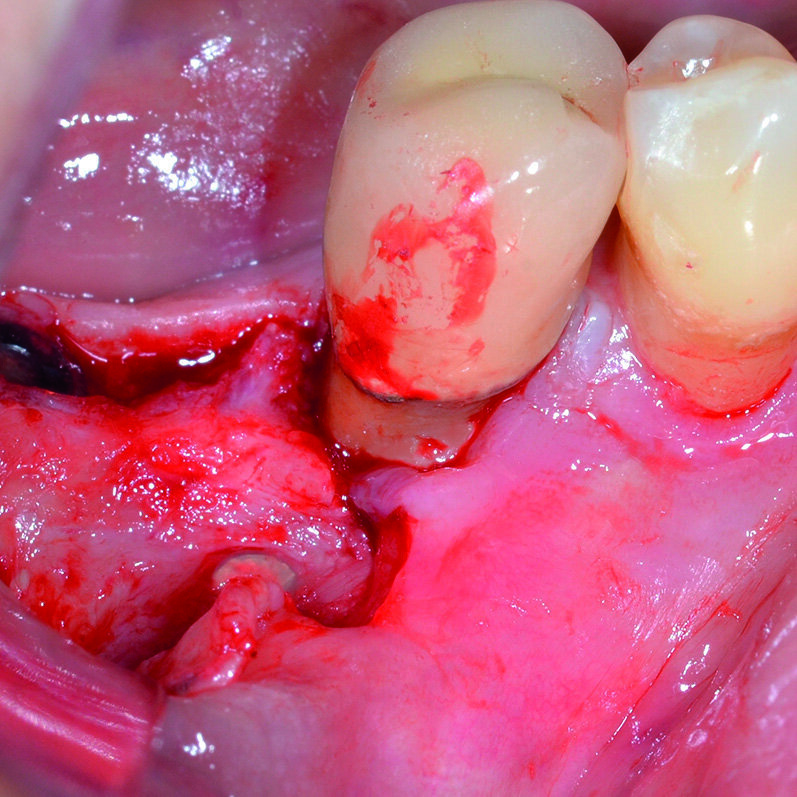

Dopo analgesia locale ottenuta per infiltrazione di Articaina cloridrato 40 mg con epinefrina 1:100.000 viene effettuata l’ incisione di accesso in accordo con il protocollo chirurgico sopra citato (Fig. 4). Al sollevamento del lembo è possibile evidenziare un profondo difetto che coinvolge l’aspetto disto-buccale dell’ elemento 4.5; con una sonda parodontale millimetrata di tipo Williams viene misurata la profondità della componente intraossea (Figg. 5-7). Il debridement della lesione e la decontaminazione della superficie radicolare vengono effettuati mediante una coppia di inserti dedicati montati su dispositivo ad ultrasuoni (ES030LDT ed ES030RDT, Esacrom Srl, Imola, Italia) (Fig. 8).

La particolarità di questi inserti è quella di avere una curvatura orientata verso destra (ES030RDT) e verso sinistra (ES030LDT): in tal modo, risulta molto più agevole operare sul versante buccale o linguale/palatale a seconda dei casi (Figg. 9, 10). Grazie all’effetto combinato della cavitazione ultrasonica e del microstreaming acustico vengono effettuati sia la rimozione del tessuto reattivo che la completa decontaminazione della superficie radicolare (Fig. 11). Al termine del trattamento con ultrasuoni, è possibile valutare l’aspetto intraoperatorio dell’area interessata dal difetto (Fig. 12).